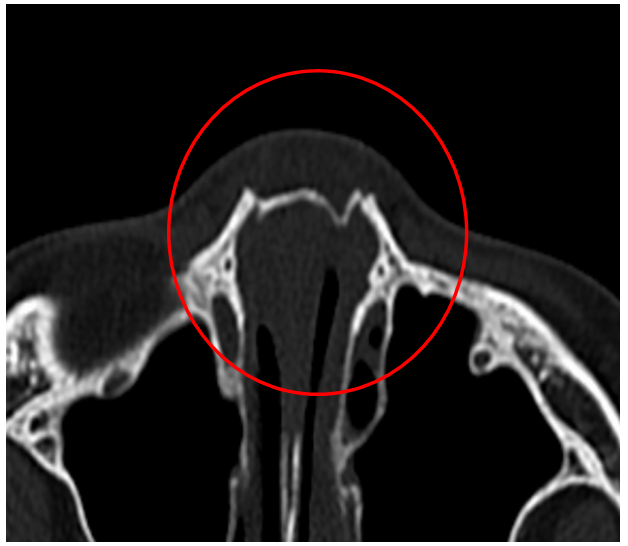

鼻骨骨折または軟骨の損傷は,腫脹,圧痛点,過可動性,crepitus(捻髪音),鼻出血,および眼窩周囲の皮下出血を来すことがある。 診断は通常臨床的に行う。 治療には,整復法,内部のパッキングによる安定化,副子固定などがある。 鼻中隔血腫は 鼻骨骨折は顔面骨骨折のなかで最も発生頻度が高く, 救急センターを併設している当院では日常診療のなかで しばしば経験する疾患である 鼻骨骨折の症状としては, 外鼻変形や鼻出血, 鼻閉が主であるが, 初診時には鼻背Class II 鼻骨と鼻中隔の他に、周辺の骨の骨折があり、粉砕骨折となっている。